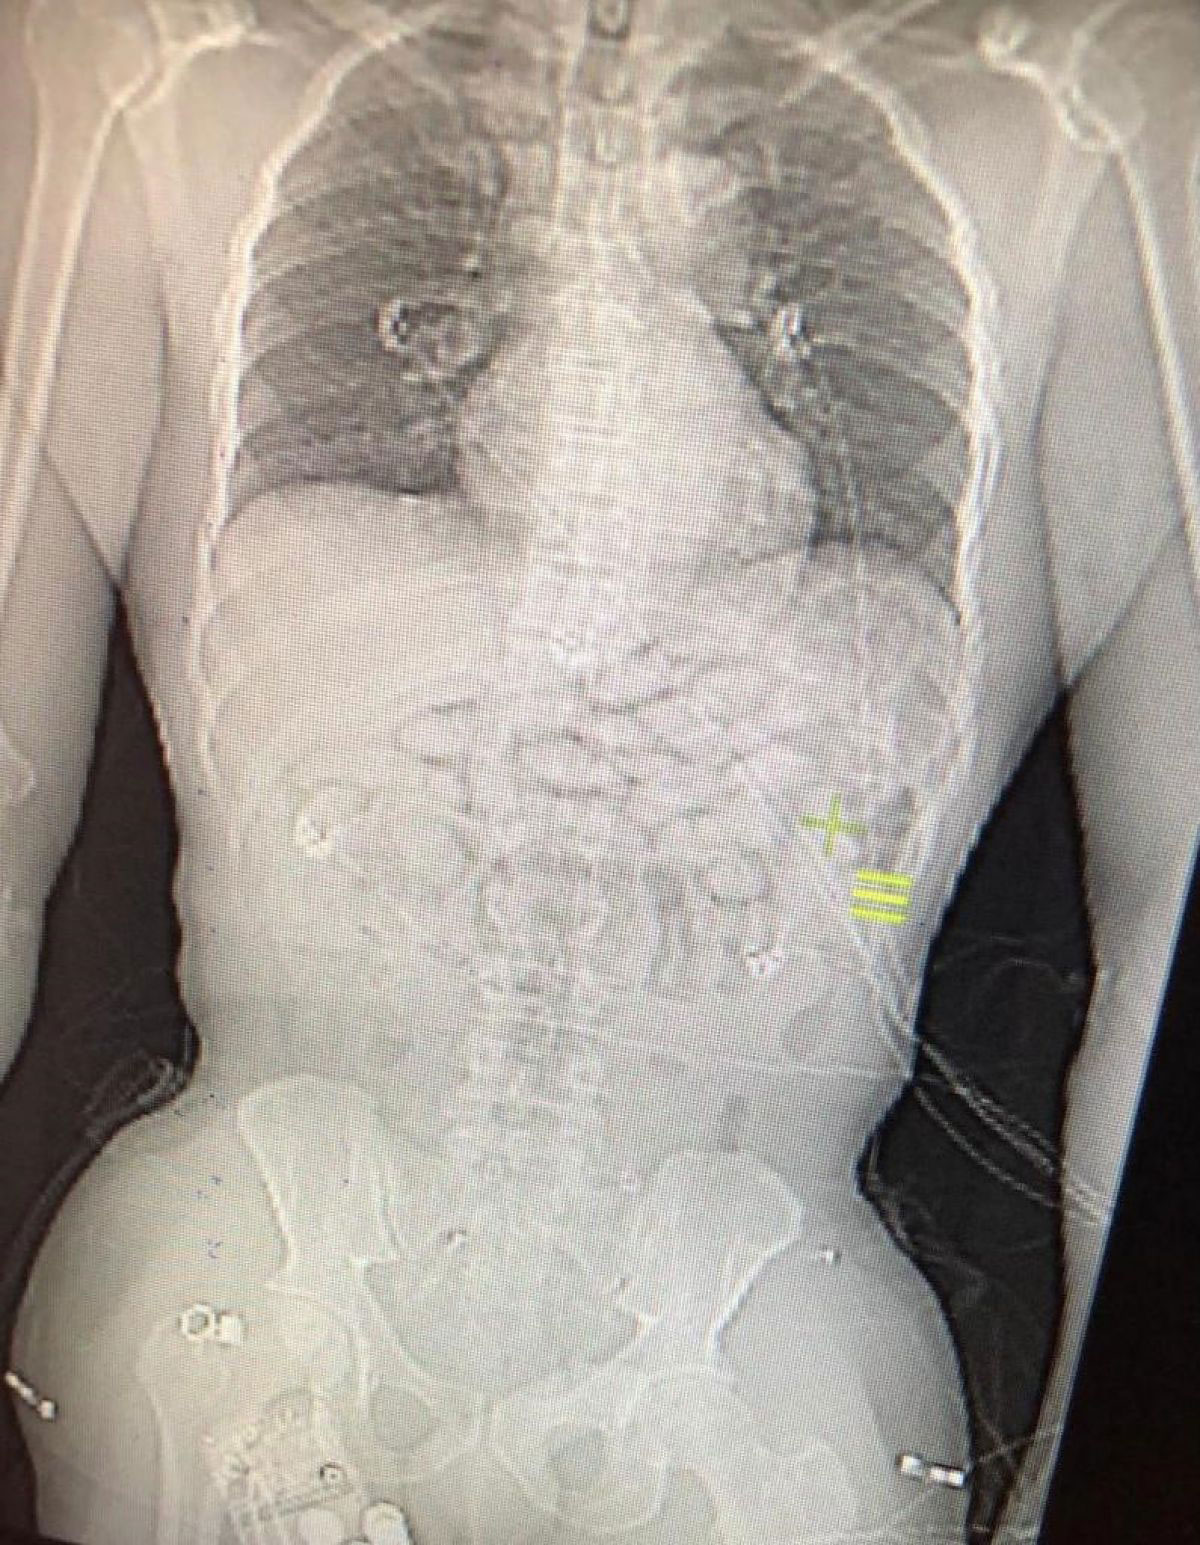

Hastanedeki kontrollerde, zanlının röntgen ile tomografi görüntülerinde midesinde kapsüllerin içine saklanmış uyuşturucu madde bulundu.

Doktorların tıbbi müdahalesinin akabinde ganalı şahsın yuttuğu içinde metamfetamin bulunan 93 tane kapsül midesinden alındı.